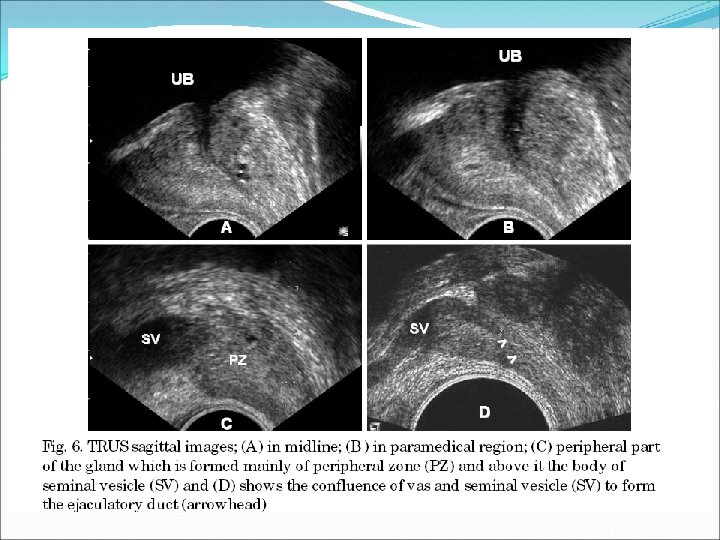

In the midplane the ejaculatory ducts are visible as hypoechoic tracts extending from the vas deferens at the base to the centrally located verumontanum. Parasagittally in men with hyperplasia the anterior hyperplastic transition zone can be seen separated from the posteriorly situated peripheral zone by the surgical capsule. The vas deferens and seminal vesicles are visible above the base. Still more laterally, the transition zone ends, leaving only the part of the peripheral zone that curves anteriorly at the sides of the glands (anterior horns). With BPH, the transition zone enlarges anterolaterally and compresses the peripheral zone into a thin, posterior rim.

TRUS TECHNIQUE It is ideal to have a small amount of urine in the bladder. Ask the patient to try and relax and "bear down" to open the sphincter as the transducer is inserted slowly. Ensure the transducer has a latex free dedicated probe cover with plenty of gel. The highest frequency sector probe 7‐ 12 MHz should be used. The scanning begins in the axial plane. The seminal vesicles are examined initially. As the probe is angled caudally the base of the prostate is seen. Once the prostate is examined in its entirety in this plane the probe is turned 90 degrees in a sagittal plane. The probe is angled from one side across to the other. A volume is taken by measuring height x length in the sagittal plane and x width in the axial plane and multiply by 0. 52. Look for changes in the contours and echogenicity in each zone.